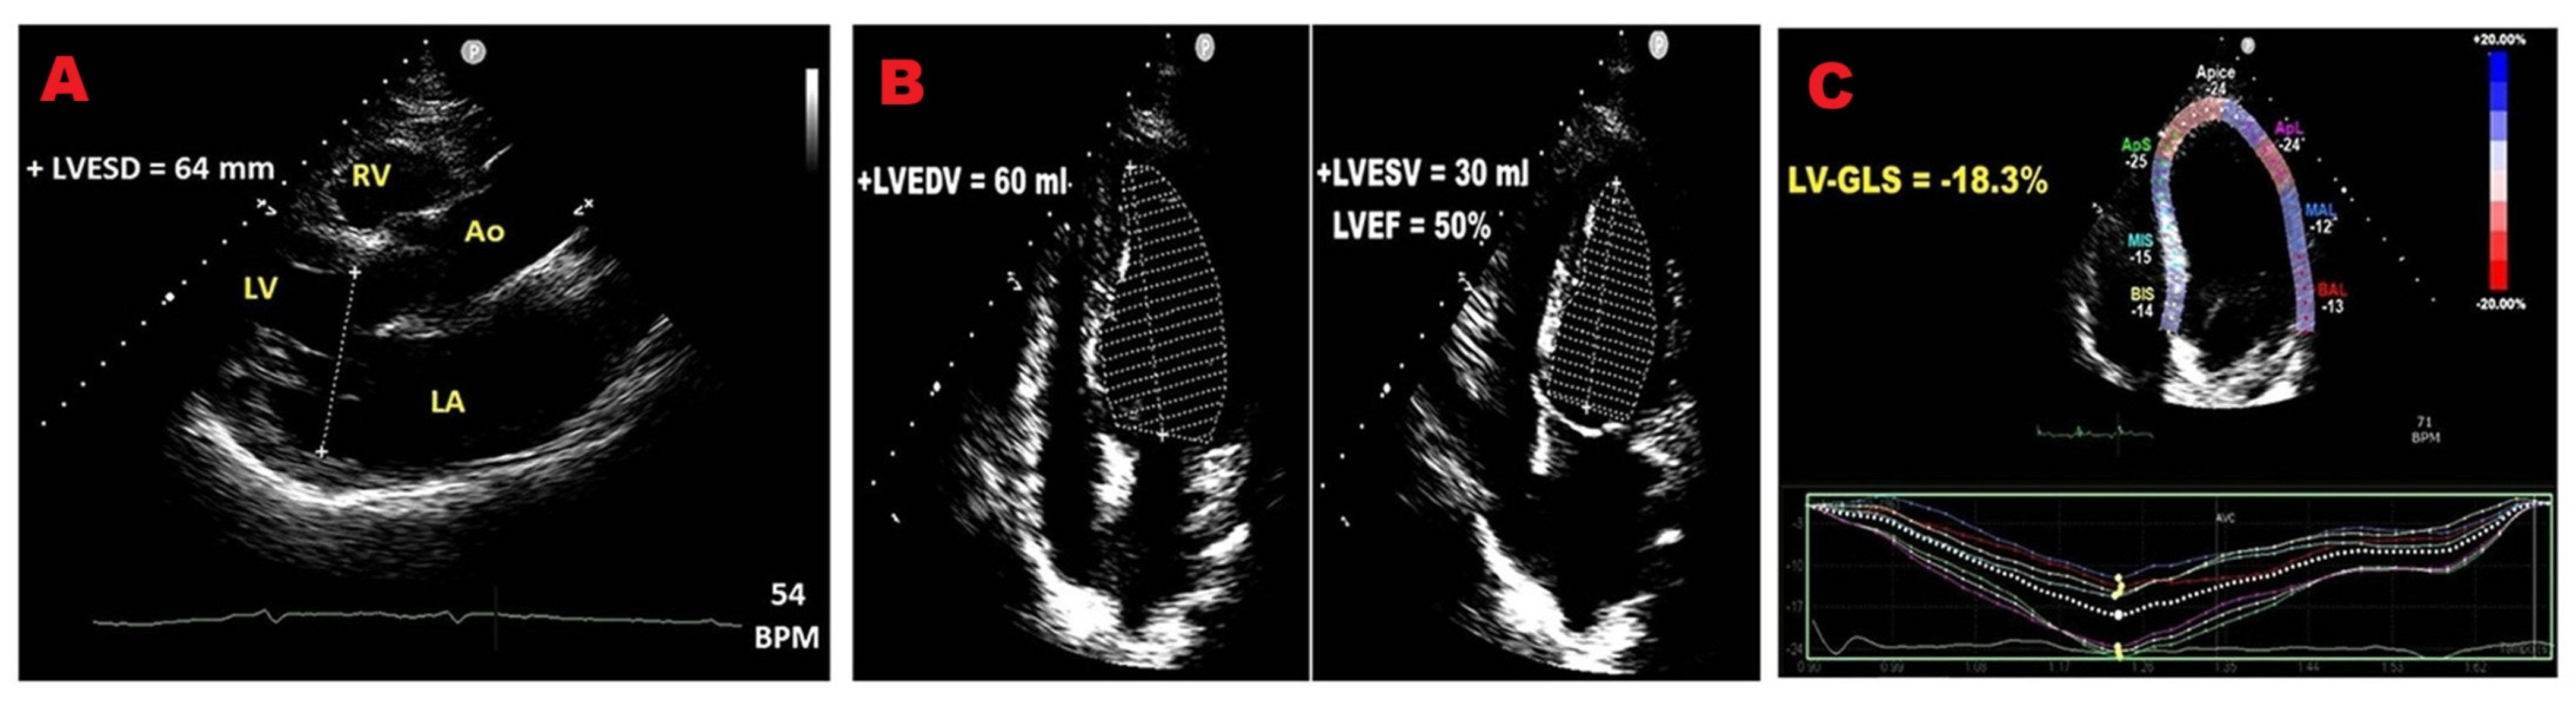

3.2. Left Ventricular Size

3.3. Left Ventricular Function

3.4. Left Ventricular Global Longitudinal Strain